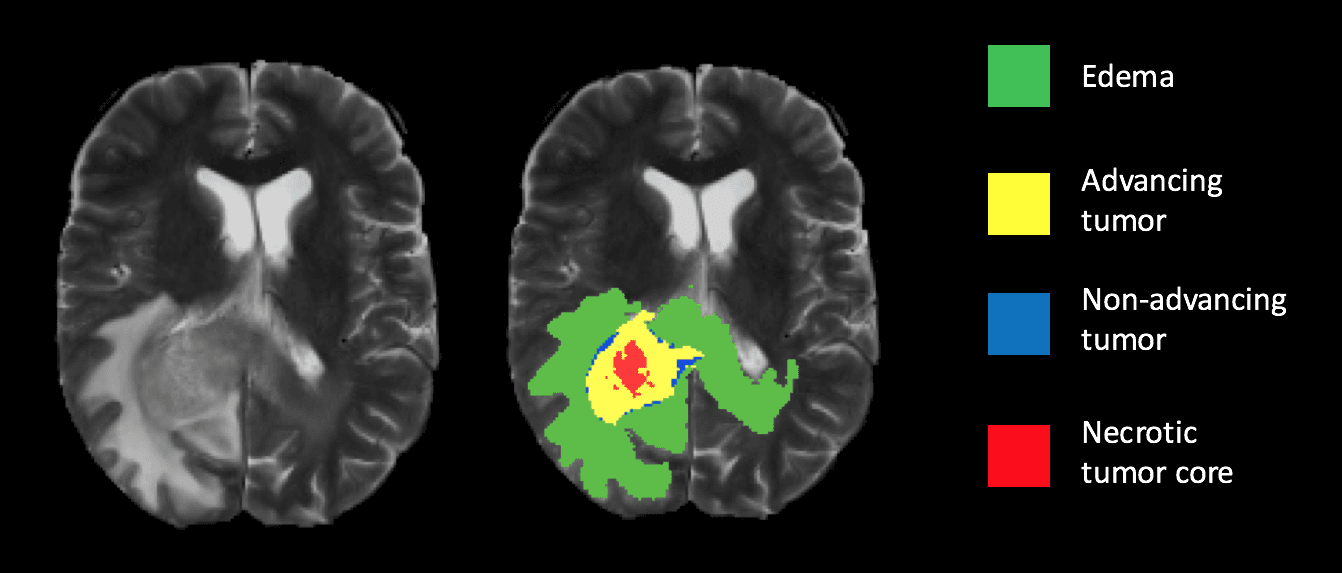

Healthcare: In medical diagnostics, semantic segmentation is revolutionizing patient care by providing precise measurements and analyses of medical imagery..

Early detection of brain tumours - Source